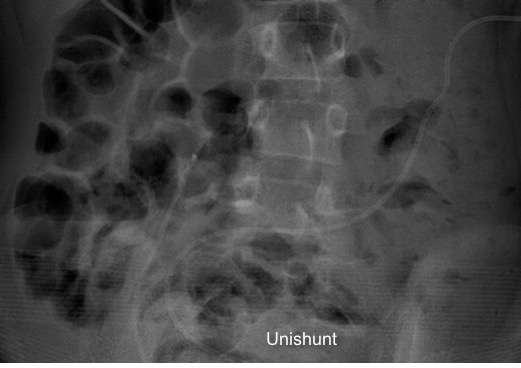

il existe un grand nombre de valves ; il n’est pas toujours aisé de les reconnaitre radiologiquement. voici la liste des plus courantes :

comment reconnaitre radiologiquement le type de valve ?